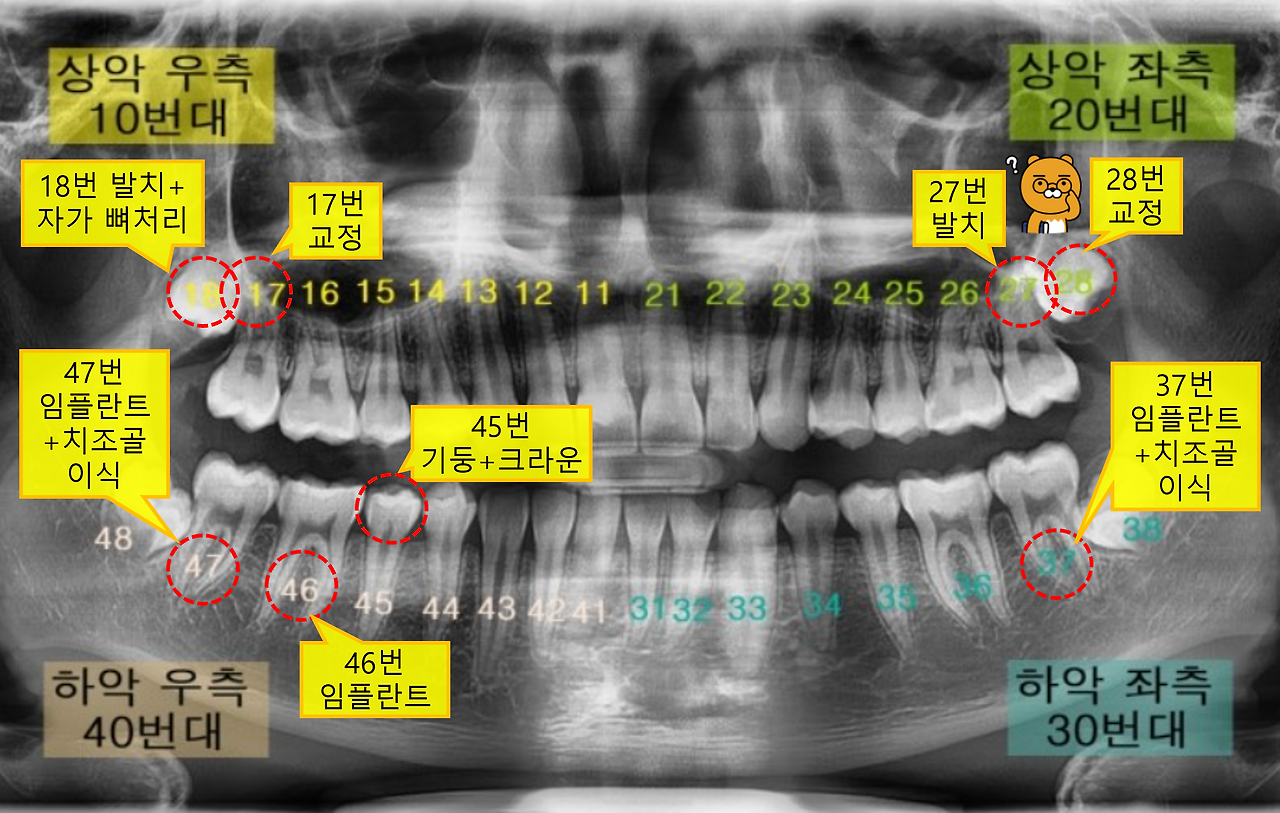

원래의 계획은 47번 치아와 18번 치아를 동시에 발치하는 것이었는데, 출혈이 많이 될 경우가 있으니 우선 47번을 뺀 후 상황을 봐서 18번도 빼기로 했습니다. 그런데 막상 47번을 뺀 후 거즈로 지혈을 해야 하는데, 이 상황에서 다시 바로 위에 있는 18번을 빼는 게 어렵다는 결론이 났습니다. 지혈을 위해서는 거즈를 물고 있어야 하는데, 위아래 치아가 동시에 없으니 거즈를 물고 있기 힘들다는 것이지요.

F7yhHqcA7ijY_rdfIGEMQAz0LwI.png [치료할 치아의 위치와 방법, 사진은 더푸른치과 자료]

첫 번째 치아를 발치한 이후 이틀 뒤에 두 번째 치아를 빼러 갔습니다. 이번에 뺀 치아는 자가 뼈 이식(치조골 이식)을 위한 것입니다. 이를 치주질환으로 인해 잇몸뼈가 소실되어 이를 메꾸기 위한 것이지요.

자가 뼈 이식의 경우 다른 이식재에 비해서 뼈의 강도가 높고 뛰어나기 때문에 임플란트 치료 시 기능이나 수명 연장에 도움이 된다고 합니다. 일단 자기 뼈이기 때문에 거부반응이나 이물반응이 없고 감염에 대한 우려도 적어 뼈가 더 잘 생성된다고 하네요. [출처: 미사센트럴치과]

발치된 치아를 뼈 이식재로 만들기 위해서는 최소 일주일 정도의 시간이 소요된다고 합니다. 가루형태의 이식재에 일부 점성을 유지하는 보조 재료가 첨가되어 있어서 재료가 응집력이 좋고, 결손 부위에 적용이 용이하다고 합니다. [출처: 바른정치과의원]